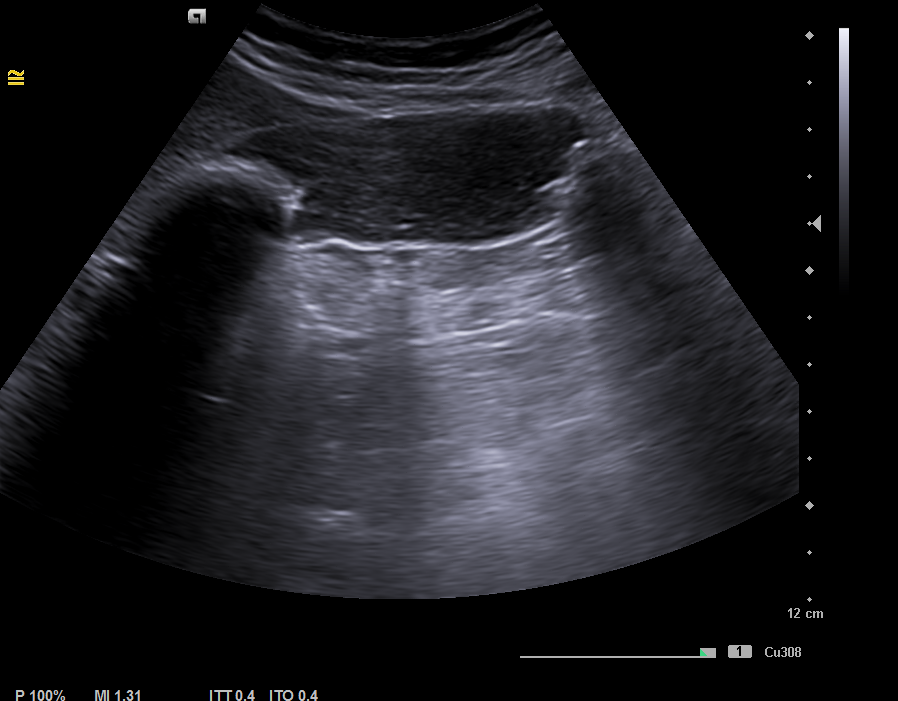

Se realiza una ecografía clínica en el momento, con calcificación en toda la vesícula, enfocando el diagnóstico en la presencia de una vesícula en porcelana y explicamos a la paciente el posible manejo.

Ante la clínica se cita a la paciente en ayunas, para conseguir una máxima distensión de la vesícula.  Se observa una imagen hiperecogénica  móvil, con sombra acústica posterior compatible con litiasis de 35 mm. Sin colección perivesicular ni dilatación de la vía biliar intrahepática y extrahepática. Hígado con ecoestructura y ecogenicidad normal, sin LOES en su interior.  Hallazgos compatibles con litiasis vesicular gigante, descartando el diagnóstico de vesícula en porcelana.